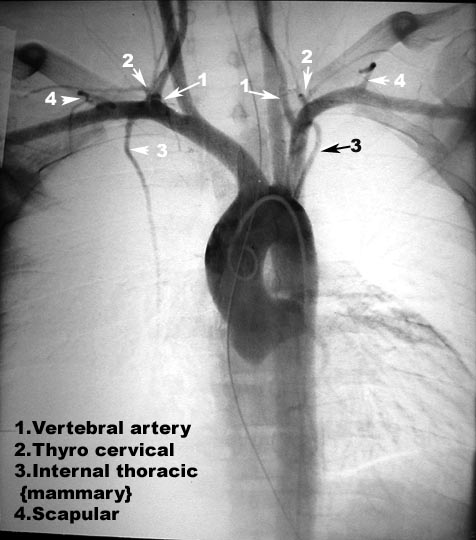

| Course | Angiogram: Origin of subclavian |

| Branches | Angiogram: Branches of subclavian artery |